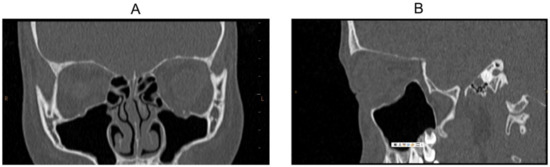

Case 9

Case 10